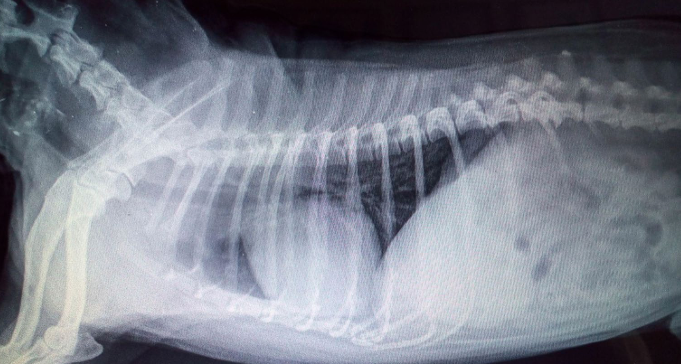

Atelectasis (Alveolar pattern)

collapsed lung